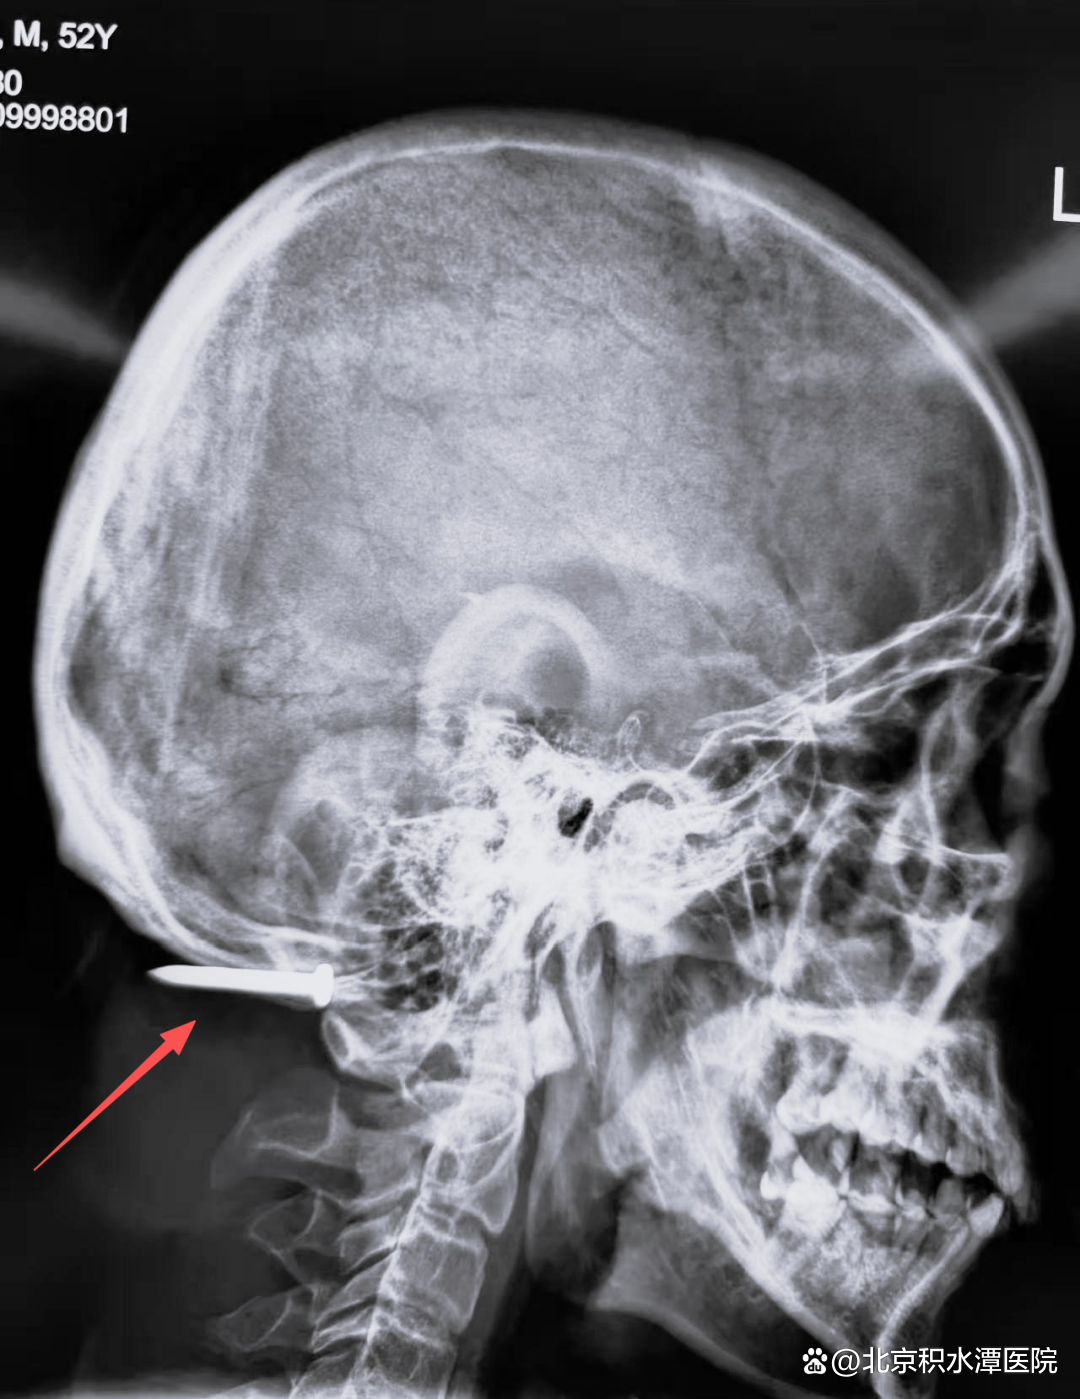

2025年11月12日中午1点,急促的救护车鸣笛声打破了北京积水潭医院回龙观院区的宁静。一名52岁男性患者被紧急送进急诊抢救室,一枚水泥钢钉从的他面部射入,贯穿颅颈部位,生命危在旦夕。

经急诊医师问诊得知,患者是一名工人,作业时不慎被射钉枪击中。射钉枪常用于钢筋混凝土施工,枪口动能巨大,导致钢钉从其左侧下颌射入,先后穿透下颌骨、口腔、颈椎间隙,最终深嵌枕部颅骨下方。伤后患者随即出现呕血症状,虽辗转多家医院,却因病情复杂、手术风险极高,最终被转至北京积水潭医院。

患者术前影像(红色箭头为钢钉位置)

检查结果进一步印证了病情的复杂性。钢钉已击碎患者高位颈椎横突,造成粉碎性骨折,更致命的是左侧椎动脉已完全断裂。“一旦术中血管破损处大出血,后果不堪设想。”经过各科室专家反复研讨、权衡利弊,最终确定了由普外科负责核心手术操作,血管外科、神经外科、脊柱外科同台保障,TICU团队给予术后支持的治疗方案。